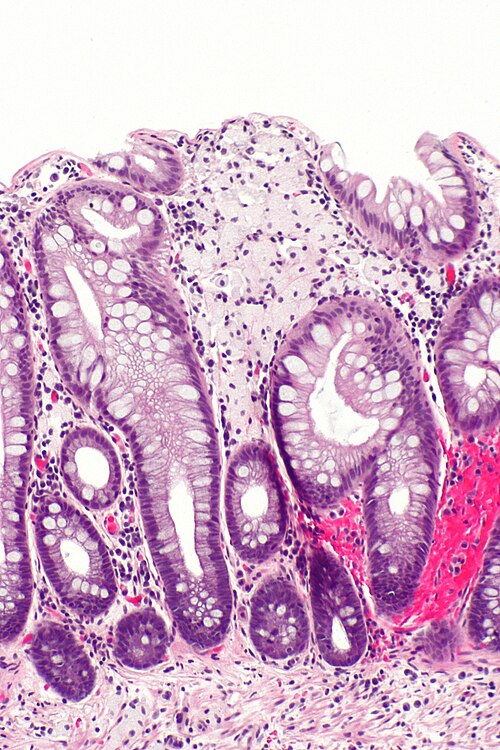

Very low magnification. H&E stain.

Intermediate magnification

Intermediate magnification. H&E stain.